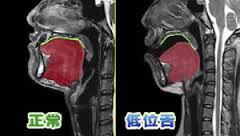

口を開けたまま食べる人は舌の位置が問題(2015.9.26)

食べている時、口の中の食べ物が見える人が、たまにいます。こういう人は、低位舌といって普段の舌の位置に問題があります。食べる時、まず前歯で噛み、それから舌で食べ物を奥歯に持っていきます。その時、舌とほっぺたで食べ物を支えて噛んでいます。食べ物が舌の上のたくさん乗っていることは、ありません。舌の上に乗ったら奥歯に送るか、すぐに飲み込むようになっています。舌が、食べ物を運ぶ働きがうまくできていないのが、低位舌です。奥に食べ物が送れていないので、前の方で噛んでいることが多いのです。口の動きを見てみると奥で噛んでいる時は、アゴは小さく横に動いています。前で食べている人は上下に大きく動かしているので余計、口が開きやすくなります。当然、くちゃくちゃし食べる音も外に聞こえるようになります。この癖はなかなか治らないので、歯医者でトレーニングを受けましょう。

Z舌の異常.png